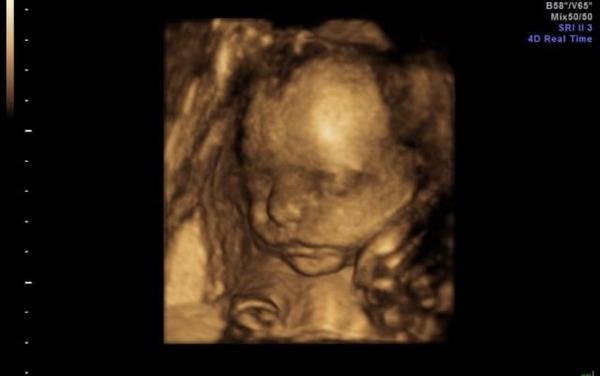

Ve 26-28.tt s obouma synama jsem byla cca v gennetu ☺️A za me parada ..u prvnihu tehu me diky tomu konecne nekdo rekl co čekame 😂

@michaelarousova nádherné fotky ❤️❤️❤️ ... mít člověk jistotu s tímto odejít, zaplatím klidně i jednou tolik ☺️

@markytkynka jooo ten druhej syn teda trochu stavkoval ale nakonec se umoudril☺️ A ta cena je vsude cca stejna ☺️